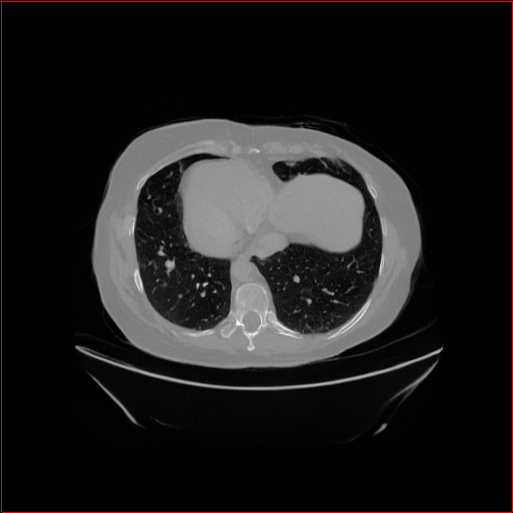

Figure 2: Qualitative comparison across axial (top row), sagittal (middle row), and coronal (bottom row) views. Columns correspond to different methods. MAISI-DDPM and MAISI-v2 in this figure are unconditional synthesis which do not use ControlNet or segmentation maps.

Qualitative Evaluation:

Figure 2 presents representative slices from the axial, sagittal, and coronal planes. GenerateCT (hamamci2024generatect) is a 2D model, so it lacks inter-slice consistency, leading to poor image quality in the sagittal and coronal views. MedSyn (xu2024medsyn) produces noticeably blurry results with mosaic-like artifacts, such as region inside the red box. HA-GAN (sun2022hierarchical) generates visually sharp images but with mosaic-like artifacts, such as region inside the red box. Also, its voxel spacing is not available, which limits its applicability in real-world medical imaging tasks. Moreover, all three methods are restricted to synthesizing small anatomical regions. In contrast, both MAISI and MAISI-v2 are capable of generating high-quality 3D volumes that span larger body regions while preserving fine anatomical details and realistic structure.